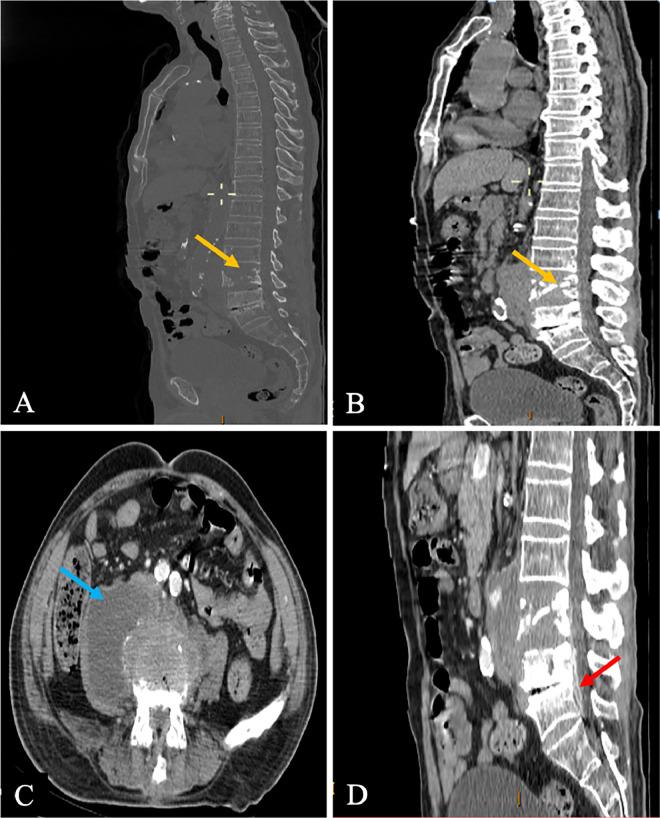

Mycotic aneurysms are a rare but potentially life-threatening complication of infections, particularly those involving the spine. Spondylodiscitis, a bacterial or fungal infection of the intervertebral disc, is a known risk factor for the development of mycotic aneurysms. Early diagnosis and prompt treatment are crucial for improving patient outcomes. We report the case of a 79-year-old patient with a history of diabetes admitted for chronic back pain refractory to medical treatment. A cervico-thoraco-abdomino-pelvic CT scan showed infectious spondylodiscitis at the lumbar level complicated by a mycotic aneurysm of the infrarenal abdominal aorta. This case highlights the diagnostic challenges associated with mycotic aneurysms, particularly when they arise from a contiguous infectious focus. Imaging modalities, such as computed tomography (CT) and magnetic resonance imaging (MRI), play a pivotal role in identifying these aneurysms and assessing their extent. The patient underwent surgical management of the spondylodiscitis and the mycotic aneurysm. A stent was placed to reinforce the weakened aortic wall and prevent rupture. Postoperative management included long-term antibiotic therapy to eradicate the infection. The patient experienced a favorable outcome, with resolution of symptoms and improved quality of life.

真菌性动脉瘤是感染的一种罕见但可能危及生命的并发症,尤其是涉及脊柱的感染。脊椎椎间盘炎,即椎间盘的细菌或真菌感染,是真菌性动脉瘤发生发展的已知危险因素。早期诊断和及时治疗对于改善患者预后至关重要。我们报告一例79岁有糖尿病史的患者,因药物治疗无效的慢性背痛入院。颈胸腹部盆腔CT扫描显示腰椎水平存在感染性脊椎椎间盘炎,并伴有肾下腹主动脉真菌性动脉瘤。该病例突出了与真菌性动脉瘤相关的诊断挑战,尤其是当它们源于相邻感染灶时。诸如计算机断层扫描(CT)和磁共振成像(MRI)等成像方式在识别这些动脉瘤及其范围评估中起着关键作用。患者接受了脊椎椎间盘炎和真菌性动脉瘤的手术治疗。放置了一个支架以加固薄弱的主动脉壁并防止破裂。术后管理包括长期抗生素治疗以根除感染。患者预后良好,症状缓解,生活质量改善。